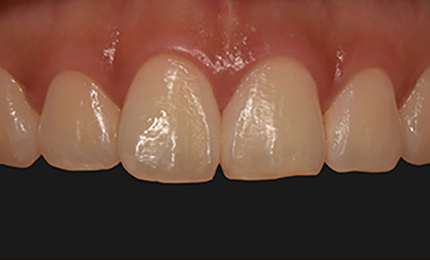

• 재 시술전

기존 보철물 제거 후 폴리싱

재 시술 후

타치과 무삭제라미네이트 후 불만족으로 인한 재시술 케이스